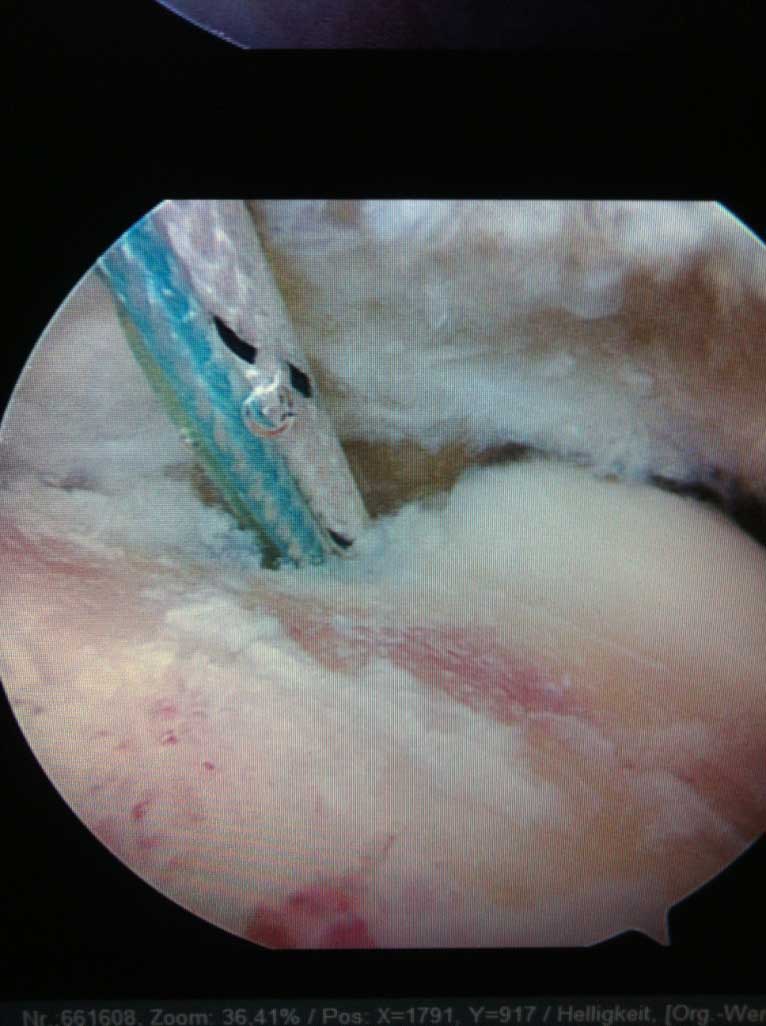

Wird die Indikation zur Sehnennaht / Rekonstruktion der gerissenen Sehnen gestellt, so wird die Operation in unseren Händen ausschließlich arthroskopisch (Schlüsselloch Operation) durch 3 - 6 kleinen Stichinzisionen (3-4mm) durchgeführt. Dieses operative Verfahren ist maximal zu den schulterumgebenden  Weichteilen schonend.

Unsere Patienten können wir sowohl ambulant in unserer OCD Klinik als auch unter stationären Bedingungen im Krankenhaus operieren.

Für ein optimales Operationsergebnis ist die anschließende krankengymnastische Behandlung zusammen mit dem s.g. Schulterstuhl (Bewegungsschiene), den unsere Patienten leihweise für einige Wochen nach Operation nach Hause erhalten, von grosser Bedeutung. Diese beiden Bestandteile der Nachbehandlung werden ausschliesslich durch uns, Ihre Operateure, für Sie, verordnet.